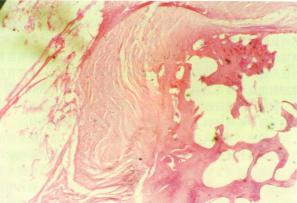

從形態學上可分為破壞性和增殖性兩類,暴髮型及局限型兩種大體可見局部頭皮腫脹,有波動感的頭皮下膿腫和慢性竇道在其鄰近的部位有單發或多發的形狀及大小不等的顱骨缺損,其中,有游離的碎骨片也可見顱骨呈凹凸不平的蟲蛀樣破壞改變病變顱骨呈灰黃色,無光澤,質松軟內含膿液。竇道內及硬腦膜外有大量黃色黏稠膿液,肉芽組織增生及硬腦膜增厚變脆。顯微鏡下可見病變組織中有大量膿球滲出及白細胞浸潤纖維結締組織及血管增生,骨小梁破壞正常結構模糊不清。

化膿性顱骨骨髓炎病理圖併發症: